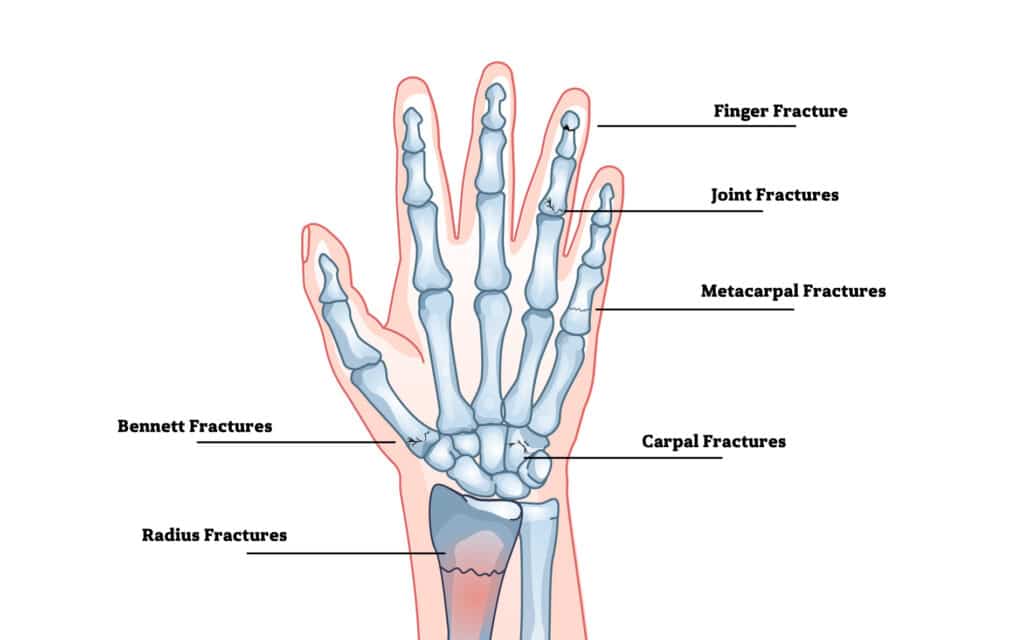

Fractures of the Hand and Wrist

Finger fractures

Bennett fractures

Radius fractures (often called Colles fractures)

Joint fractures of the fingers

Metacarpal fractures

Carpal fractures